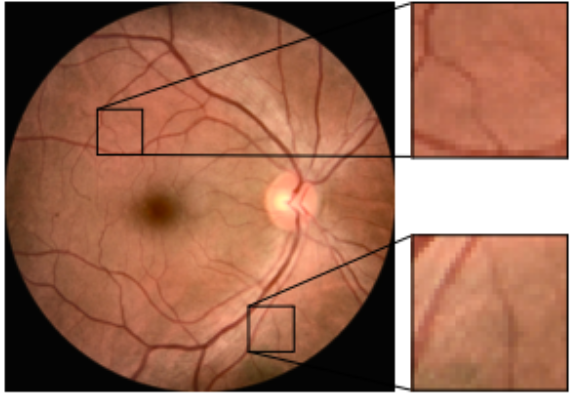

眼底图 fundus:

眼底图(Fundus Imaging):

- 用途: 眼底图是通过特殊的摄影技术捕捉眼球内部后部的图像,包括视网膜、视盘和黄斑等结构。

- 优点: 眼底图在诊断和管理诸如糖尿病视网膜病变、青光眼、视网膜脱落和年龄相关的黄斑变性等疾病中非常有用。

- 从临床选择了一组单独的病例集(OCT图像+眼底图像),将一个眼科专家团队根据其OCT图像做出的诊断标注作为黄金标准,然后用相对应的眼底图像组成测试集,由鹰瞳Airdoc独立研发的AI算法模型和其他眼科医生分别给出判读。

- 以OCT诊断为标准诊断,AI眼底彩照识别模型的AUC为0.8566,其敏感性和特异性比人类医生更加均衡和出色

- 基于眼底照片的AI分析可作为ERM筛查中人类医生诊断的替代方案,患者在难以获得眼科专家看诊或先进检查的情况下,能以相对较低的成本取得较好的诊断准确性。

- 尽管OCT图像是ERM诊断的黄金标准,但眼底照片也为诊断提供了有价值的增益信息。基于眼底照片研发的AI模型,在实际临床场景具有良好的性能。